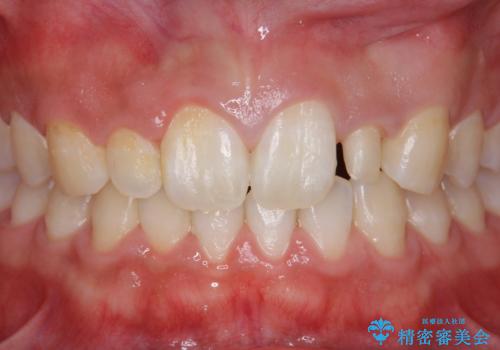

前歯のすきま 矯正治療とセラミックで小さな歯を形良く

- 前歯のすきまを気にして来院。

左上の2番が生まれつき小さく、スペースが余っていました。

右上の2番もやや小さめでしたが、相談の上、左上2番のみセラミックで形を整えることとしました。

そのほかの隙間はマウスピース矯正で閉じることにしました。

当初はワイヤー矯正を希望されていましたが、右上7番の頬側に咬頭があり、ブラケットを貼ることが難しいため、こちらからマウスピース矯正をお勧めしました。